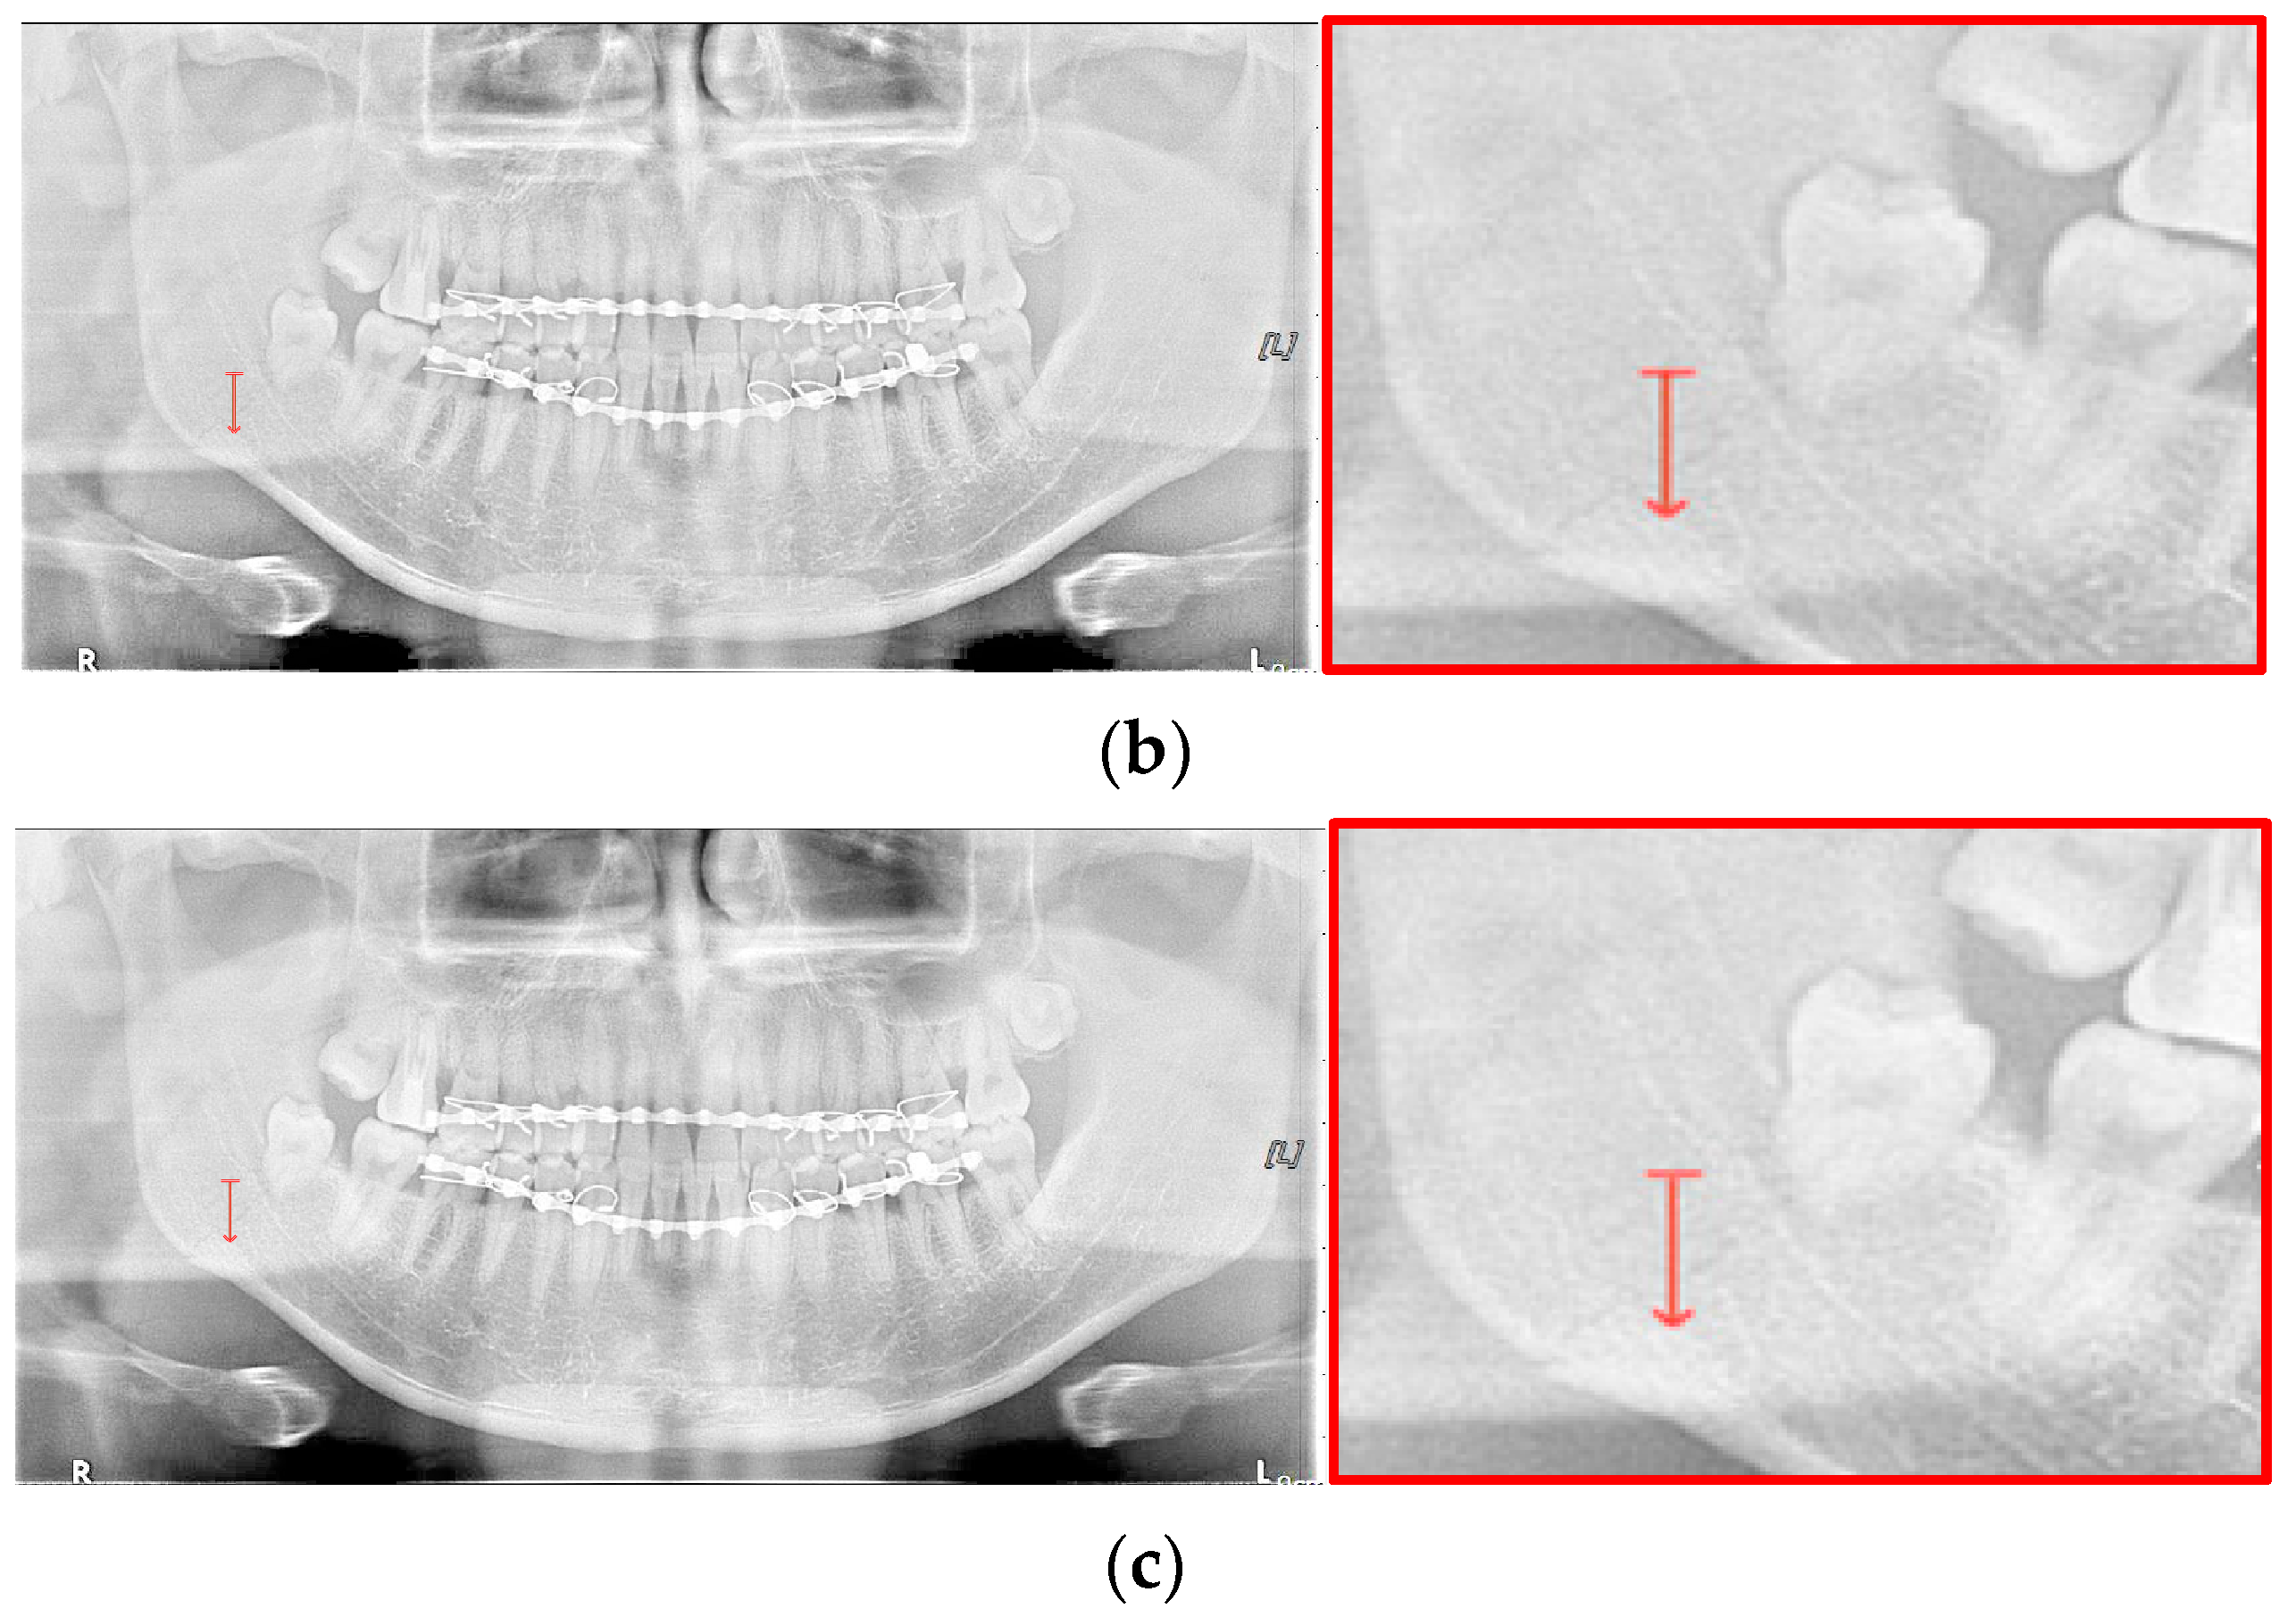

For the case of Figure 12 images, it is possible to check the amount of local contrast improvement from the line profile information. In order to compare the changes in pixel brightness near angle fracture in the normal, SLAT and MLAT panoramic radiographs, the result of line profiles are shown in Figure 14 and Table 7. When comparing the maximum pixel brightness, minimum pixel brightness, average pixel brightness, and standard deviation in the line profile of the straight arrow near the angle fracture site, the normal panoramic radiograph has the largest standard deviation value of 5.6. Due to the characteristics of LAT processing, a dark area increases contrast, but as it becomes a bright area, contrast is maintained or slightly lowered.

Figure 14.

However, except for some bright radiograph images, the effect of LAT processing is evident in most dark radiograph images. As shown in Figure 15, most of the LAT-processed radiographs have a high standard deviation value compared to the normal radiographs. In Table 7, the LAT-processed panoramic radiographs shows the higher deviation values of 14.6 and 15.2, which are reasonably more than 9.3 of the normal panoramic radiograph.

Figure 15.

The comparison of SLAT and MLAT processing with line profiler: (a) normal radiograph, (b) SLAT processed, and (c) MLAT processed.